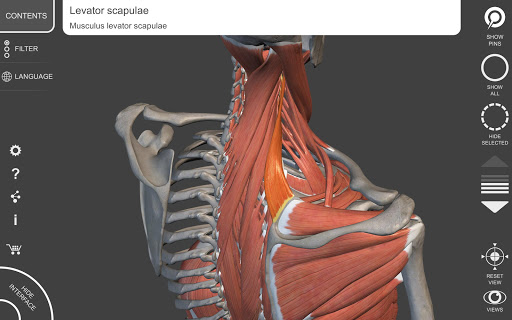

يتيح لك "Anatomy 3D Atlas" دراسة التشريح البشري بطريقة سهلة وتفاعلية.

من خلال واجهة بسيطة وبديهية، من الممكن ملاحظة كل بنية تشريحية من أي زاوية.

تتميز النماذج التشريحية ثلاثية الأبعاد بتفاصيل خاصة ودقة تصل إلى 4K.

يسهل التقسيم حسب المناطق والمناظر المحددة مسبقًا مراقبة ودراسة الأجزاء الفردية أو مجموعات الأنظمة والعلاقات بين الأعضاء المختلفة.

• تصور العضلات من خلال مستويات الطبقات من الطبقات السطحية إلى الأعمق

• من خلال تحديد نموذج أو دبوس، يظهر المصطلح التشريحي ذي الصلة

• وصف العضلات: الأصل والإدخال والتعصيب والعمل